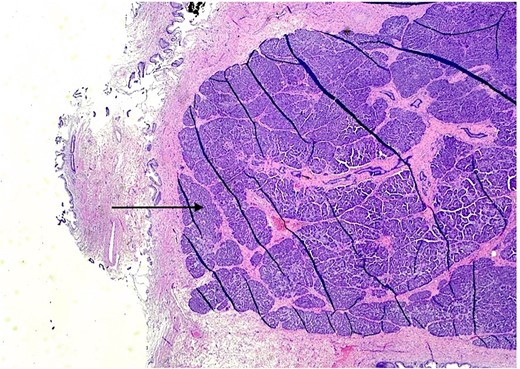

The patient underwent an elective laparoscopic cholecystectomy. During the surgery, findings were consistent with chronic cholecystitis. No abnormalities were visible upon gross inspection. Postoperatively, the patient recovered well and was discharged on the same day. The macroscopic histopathological examination revealed an intact GB with pink serosa. The mucosa was yellow-red without focal lesions. The microscopy showed chronic cholecystitis and the presence of a 1 cm focal nodule in the GB wall compatible with ectopic pancreatic parenchyma containing only acinar and ductal components (Figs 2–3). There was no evidence of dysplasia or malignant transformation in the analyzed sections. Since no malignancy was found among the EPT, there was no need for further treatment.

H & E stain 20×: Ectopic pancreatic parenchyma, composed of ductal and acinar components (black arrow).

H & E stain 20×: Ectopic pancreatic parenchyma (black arrow), present in the gallbladder wall, composed of mucosa with underlying muscularis and adventitia (red arrow).